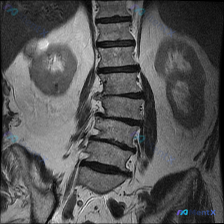

整理到一份有意思的病例资料: - 影像端:肾脏MRI T2加权冠状位提示右肾上极圆形高信号影,边界清、信号均、无壁结节/分隔,符合单纯性肾囊肿(Bosniak I级)的影像学表现;双肾其余结构、集合系统、肾周间隙基本正常。 - 临床背景:明确存在脊柱侧弯(Scoliosis)。 问题来了:如果只看肾...